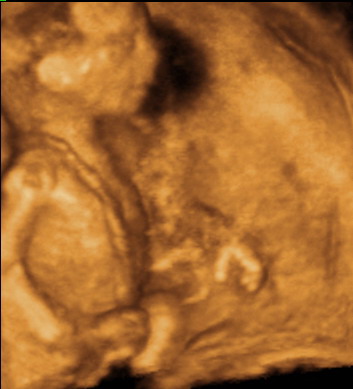

KépKép

Ja, és a méhfájdalom! Én időnként érzem, hogy növekszik a méhem, és szedem is a magneb6-ot, de szerintem nálam már mint placebo is működik, mert a napi szükséglet töredékét tartalmazza, mégis 1-2 szemtől azonnal elmúlik :wink: !

Viszont éjszaka egy-egy fordulásnál bele szokott nyilalni a fájdalom a méhszalagjaimba. Tegnap este pl. jobb oldalon úgy belenyilalt, hogy kb. ez játszódhatott le az arcomon: :shock: :shock: :shock: :x :cry: :cry: :x :shock: :shock: :shock: